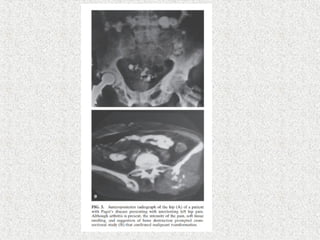

 2-4% in symptomatic

 0.1% overall

 Humerus –common site for malignant change

 Benign tumor

 GCT

 Sensitive to steroid therapy

 Malignant

 Osteogenic sarcoma(poor prognosis)

 Fibrosarcoma

 chondrosarcoma

 Signs

 More painful/tender/swollen

 New pain

 New site

 New Lytic area in sclerotic bone